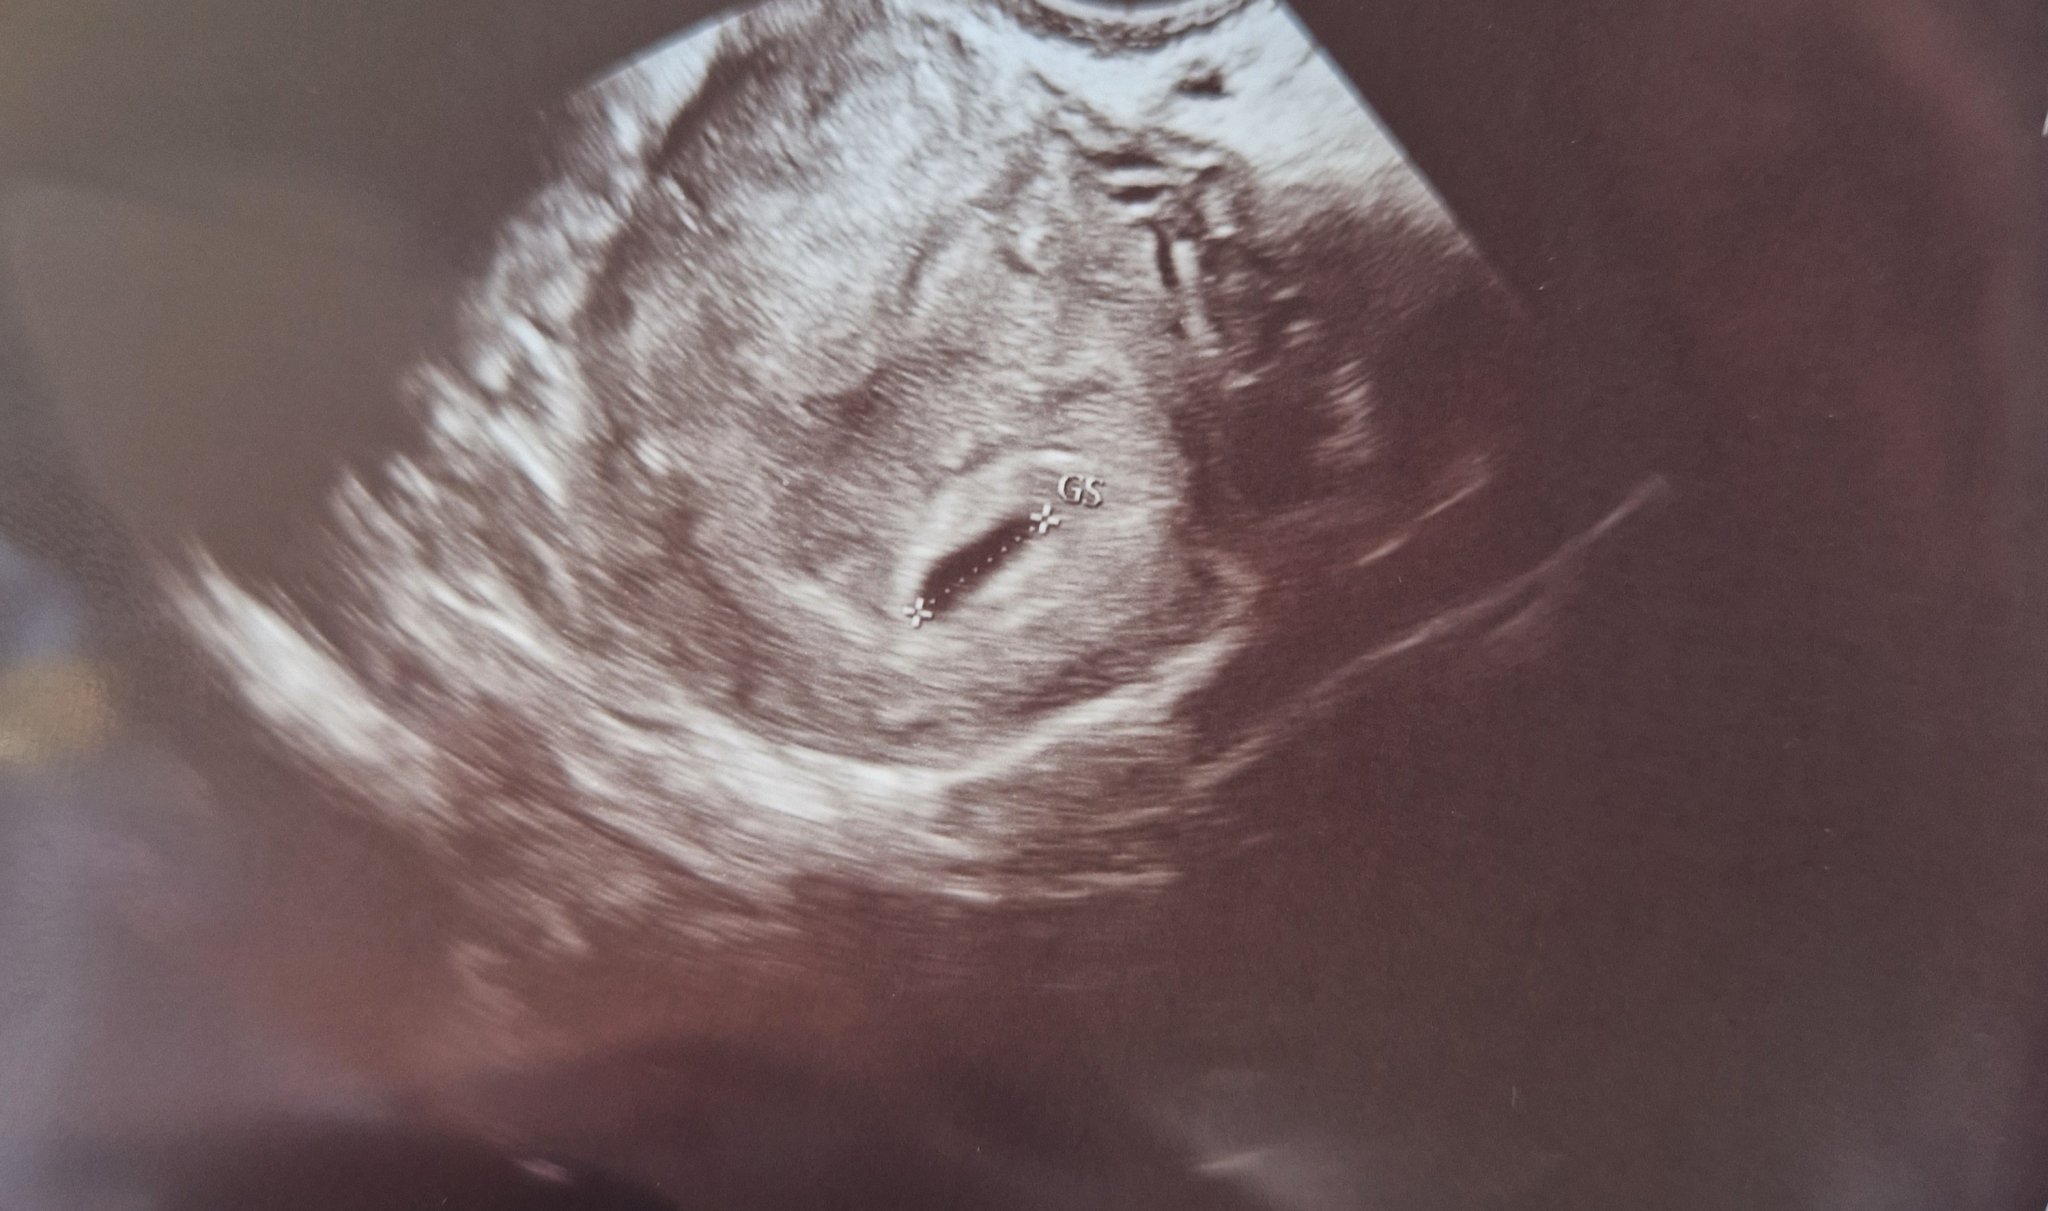

Здравейте, в ранна бременност съм и прилагам снимки от прегледите - първата е 5+6 г.с , а втората е 6+4  г.с. като е очевидно, че расте и има сърдечна дейност. Въпроса е, че матката ми явно е стегната и формата му продължава да е такава като при първия преглед ми изписаха дуфастон, а при втория преглед ми добавиха и но шпа като при въпроса ми, че формата не би трябвало да е такава отговора от лекаря е, че расте и се развива, което не знам дали трябва да ме успокоява. Има ли някой тук, който да е минал през същото нещо Confused